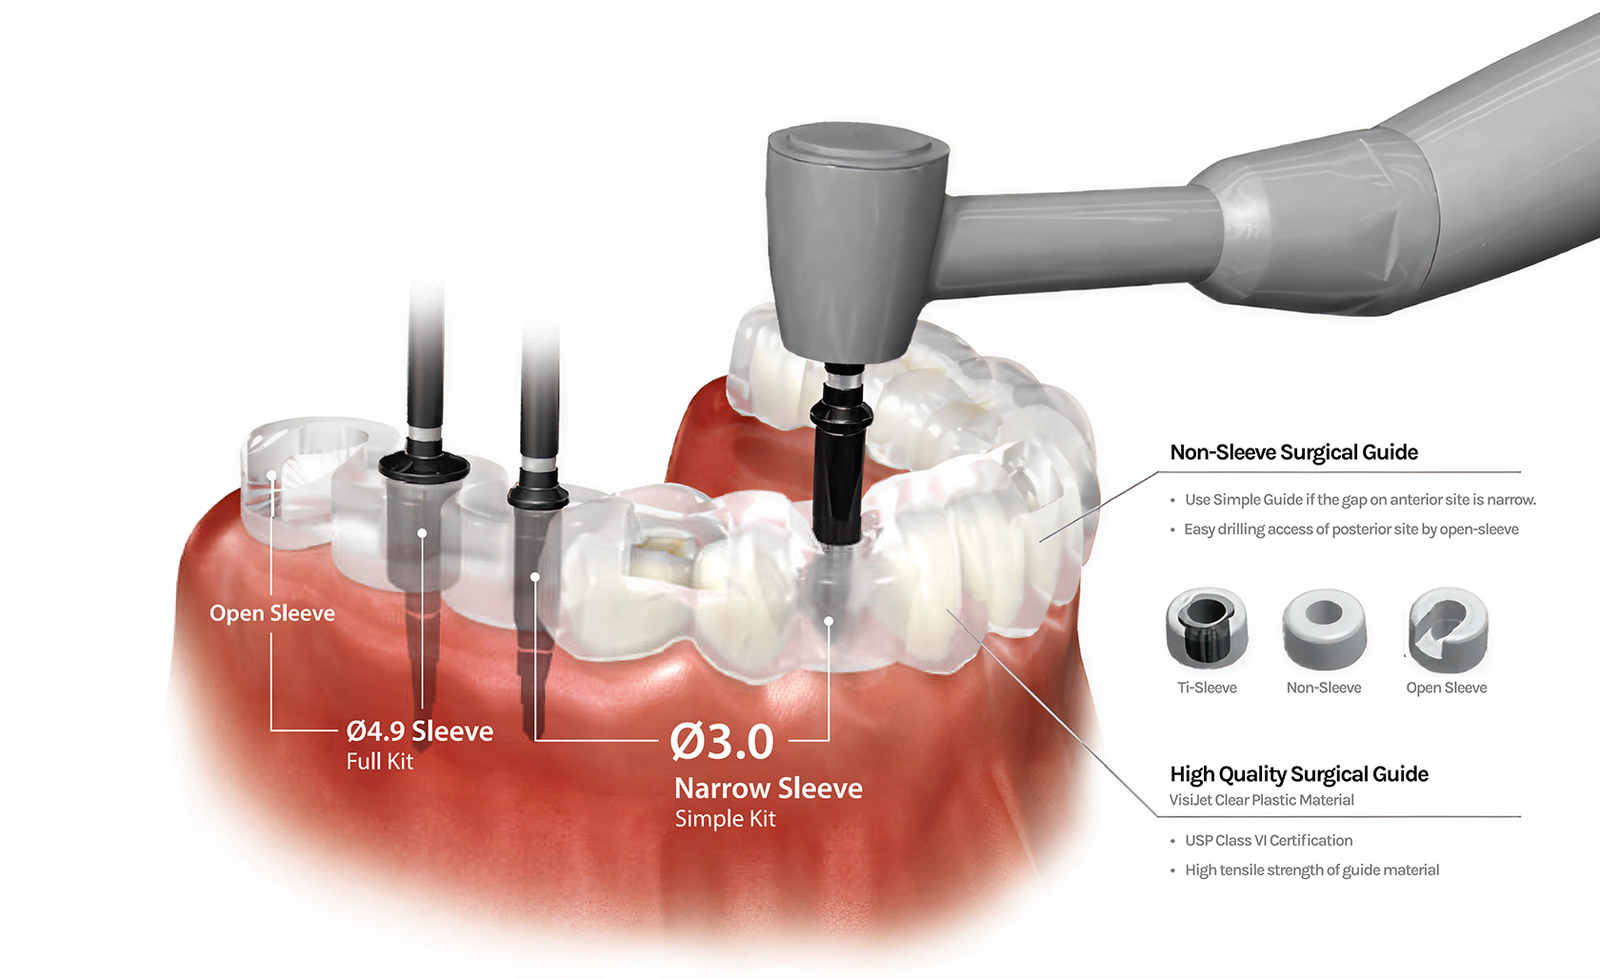

Surgical Guide Setting

Create Surgical Guide

Add Support Bar, Viewing Window